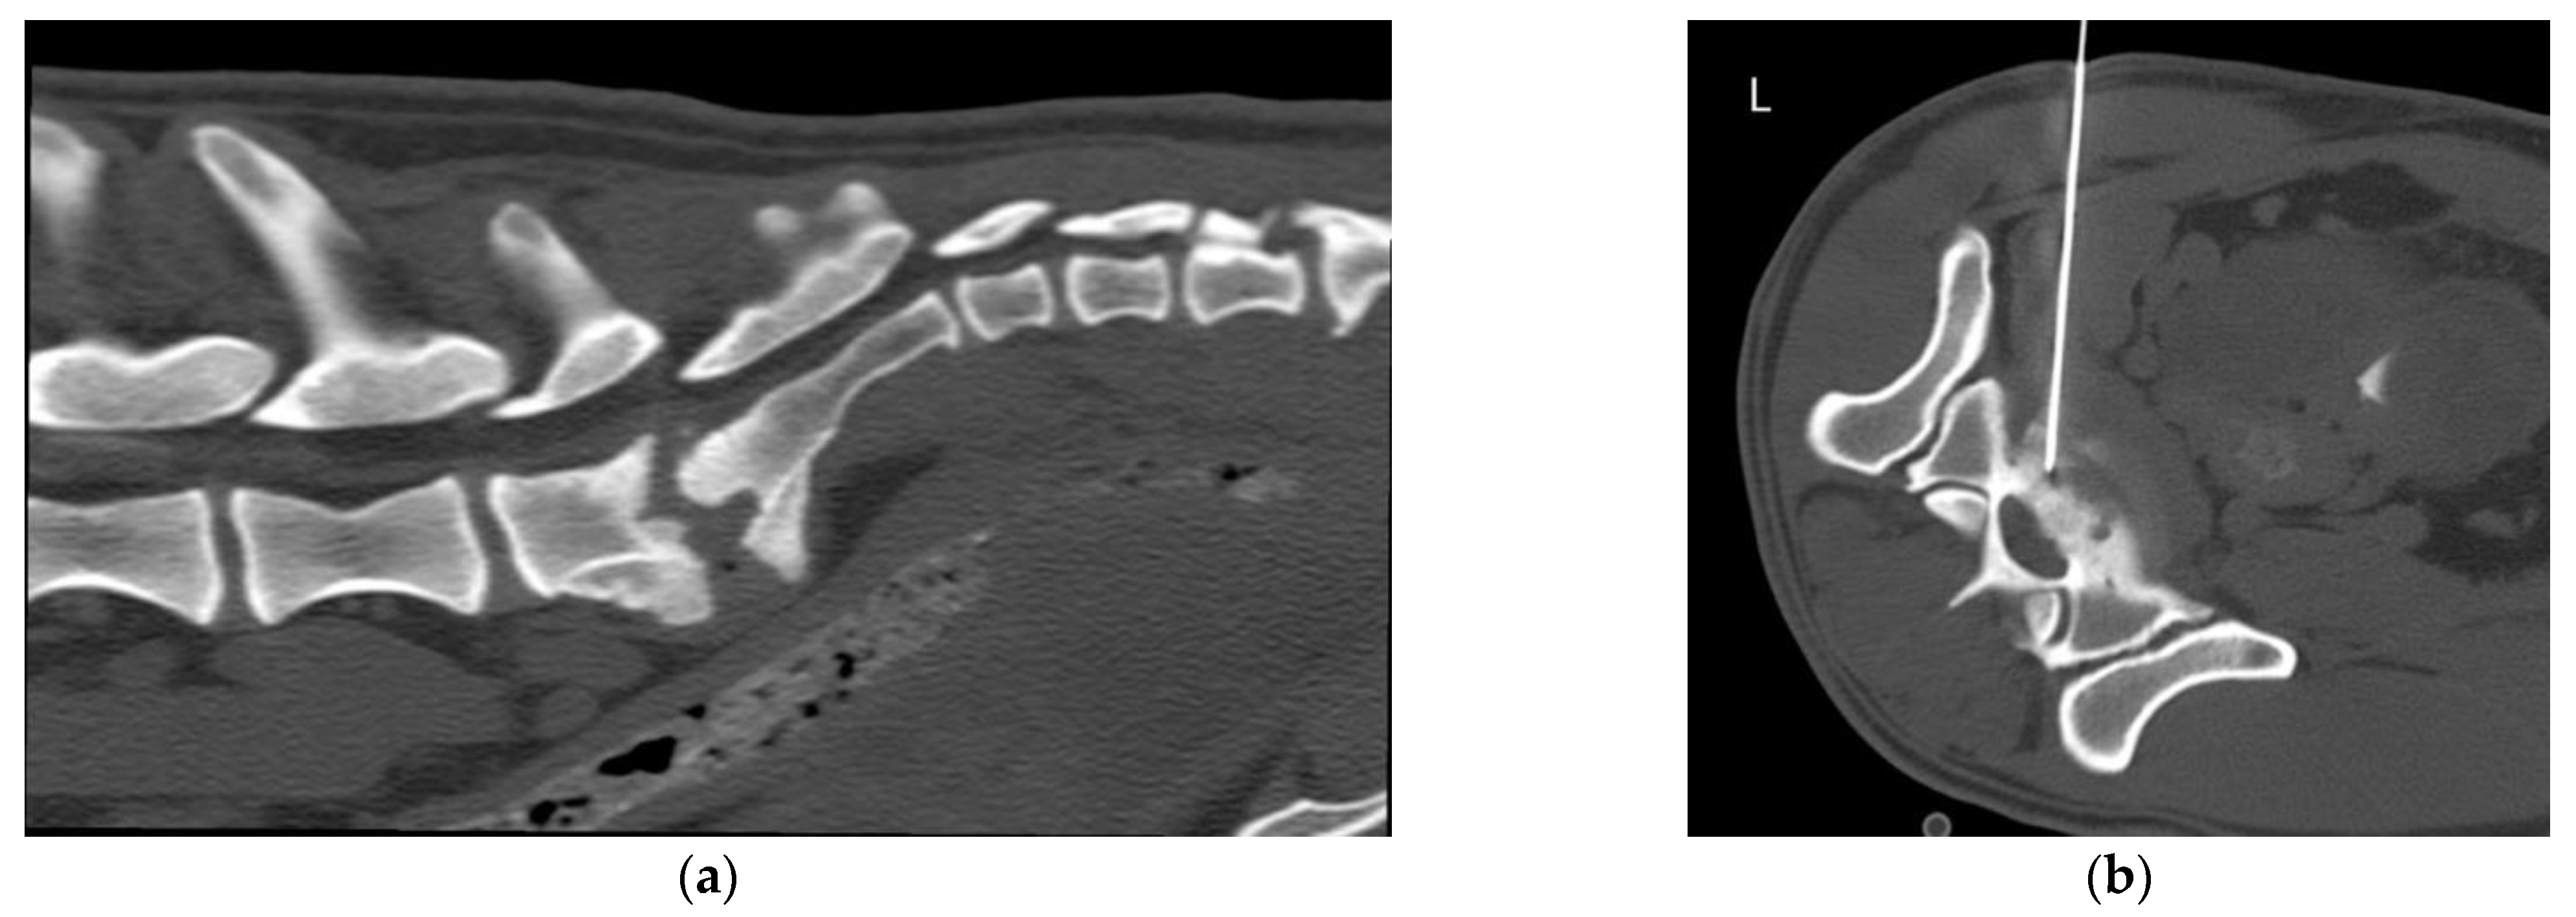

2.2. Equipment and Technique

| 1 | Canine German shepherd dog Male intact 7 yo | Chronic progressive hindlimb weakness | NE: absence of postural reactions (PR) in both HLs, normal spinal reflexes (SR) and thoracolumbar hyperesthesia NLoc: T3-L3 myelopathy | Polyostotic aggressive bone lesion (mainly lytic) in L3 and L4 articular processes, laminae and pedicles, mostly right-sided. Non-primary bone tumor, synovial cell sarcoma | Right L4 cranial articular process | Mesenchymal tumor consistent with sarcoma | |

| 7 | Canine Cross breed large Female neutered 10 yo | Chronic and progressive history of severe cervical hyperesthesia, TL kyphosis | NE: Ambulatory tetraparesis worst in the HLs; absence of PR with normal SR in all four limbs. Severe hyperesthesia in the C- and TL- spine. NLoc: multifocal C1–C5 and T3-L3 myelopathy | Multifocal aggressive lesions centered in the IVDS of the C- and T- spine, worst at C6–C7 and T11–T12. Subluxation at C6–C7. Severe endplate osteolysis, sclerosis and narrowing of the IVDS. Marked NBF. Discospondylitis (chronic) | IVDS at T11–T12 | Discospondylitis by Pseudomona aeruginosa | - |